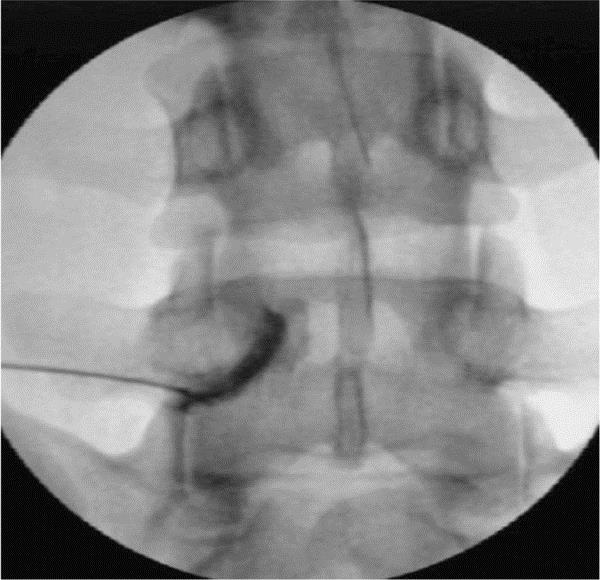

神经根/背根神经节阻滞联合脉冲射频镇痛术